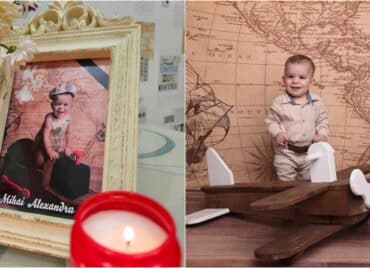

Un bebeluș a murit la două zile după naștere. Acuzații grave de malpraxis la Spitalul din Slatina. Părinții unui bebeluș din Slatina lansează acuzații dure la adresa medicilor de la Spitalul Județean.

Soții Calcan acuză cadrele medicale de neglijență, după ce fetița lor a murit la doar două zile de la naștere.

Aparent, copilul nu a avut probleme la naștere, însă starea de sănătate i s-a înrăutățit brusc. Medicii i-au anunțat pe părinți că fetița lor are nevoie de oxigen, iar Spitalul Județean Slatina nu avea aparatura necesară pentru a stabiliza starea bebelușului.

Un bebeluș a murit la două zile după naștere. Acuzații grave de malpraxis la Spitalul din Slatina

„De la 10 a suportat alteraţia plămânului şi până la ora 3:00 nu au încercat. Tocmai la 3:00 s-au gândit că trebuie să o ducem la Bucureşti”, a declarat Mihăiță Calcan, tatăl bebelușului pentru digi24.ro.

Medicii au avut timp 9 ore să găsească o soluție

Starea fetiței se altera de o oră la alta, iar medicii ar fi trebuit să o transfere în regim de urgență la București.

Până când au hotărât în mod oficial cum să procedeze în cazul fetiței, a fost prea târziu.

După nouă ore, la spitalul din Slatina a sosit o salvare dotată corespunzător care urma s-o transporte la București. Fetița, însă, murise.

„Trebuie precizat că rangul maternităţii noastre ne permite observația pacientului timp de trei zile. Poate o să vă întrebaţi de ce pacientul nu a fost transferat imediat, dar iniţial pacientul a avut o situaţie favorabilă care nu a necesitat transferul.

Ulterior sunt consemnate toate demersurile noastre de transfer şi a fost trecut în foaia de observaţie şi nu pot să vă spun de ce nu s-a realizat acest lucru”, a declarat Radu Ene, director medical la Spitalul Slatina.

Din primele informații, mama fetiței născuse în regim de urgență prin cezariană.

Tatăl fetiței decedate a depus plângere la Colegiul medicilor, la Parchetul de pe lângă Tribunalul Olt și la Poliție, iar oamenii legii au început deja o anchetă.

Conducerea spitalului județean Slatina a declanșat propria anchetă în acest caz.